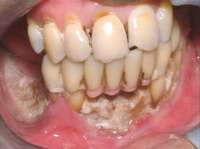

For patients on IV bisphosphonates, after bone is exposed, it is almost impossible to cover.15 Most cases worsen if surgical intervention is performed. Most patients must simply deal with the exposed bone and keep it clean so that bacterial infection does not occur. Figure 2 and Figure 3 show a postmetastatic prostate cancer patient with exposed bone. The treatment plan for this patient was to make a soft-lined denture that would not put pressure on the exposed bone and to check for bacterial infection on a routine basis. When dealing with patients on or about to begin IV bisphosphonate therapy, dentists need to be very astute. As stated earlier, this form of the drug has a much higher incidence of complications. These patients are often very sick and immuno-compromised and, therefore, must be managed properly. Pre-IV bisphosphonate patients (ie, those not yet receiving the drug) are much easier to manage than patients already receiving the drug. First, ask the treating physician, usually an oncologist, if he or she can wait 2 months before the drug is given. If the cancer is severe, it may not be possible to wait. Dentists should make use of whatever time can be made available before bisphosphonate treatment begins.16 This time should be used to get a full-mouth series of radiographs and to remove all dental infections, including all decay. If decay cannot be removed completely, the tooth should be considered for extraction. Before IV therapy begins, patients are at a lower risk for extraction complications than they are during bisphosphonate therapy.

Figure 2 and Figure 3 Postmetastatic cancer patient with BRONJ (A) in the lower right quadrant and (B) in the lower left quadrant.

Figure 3